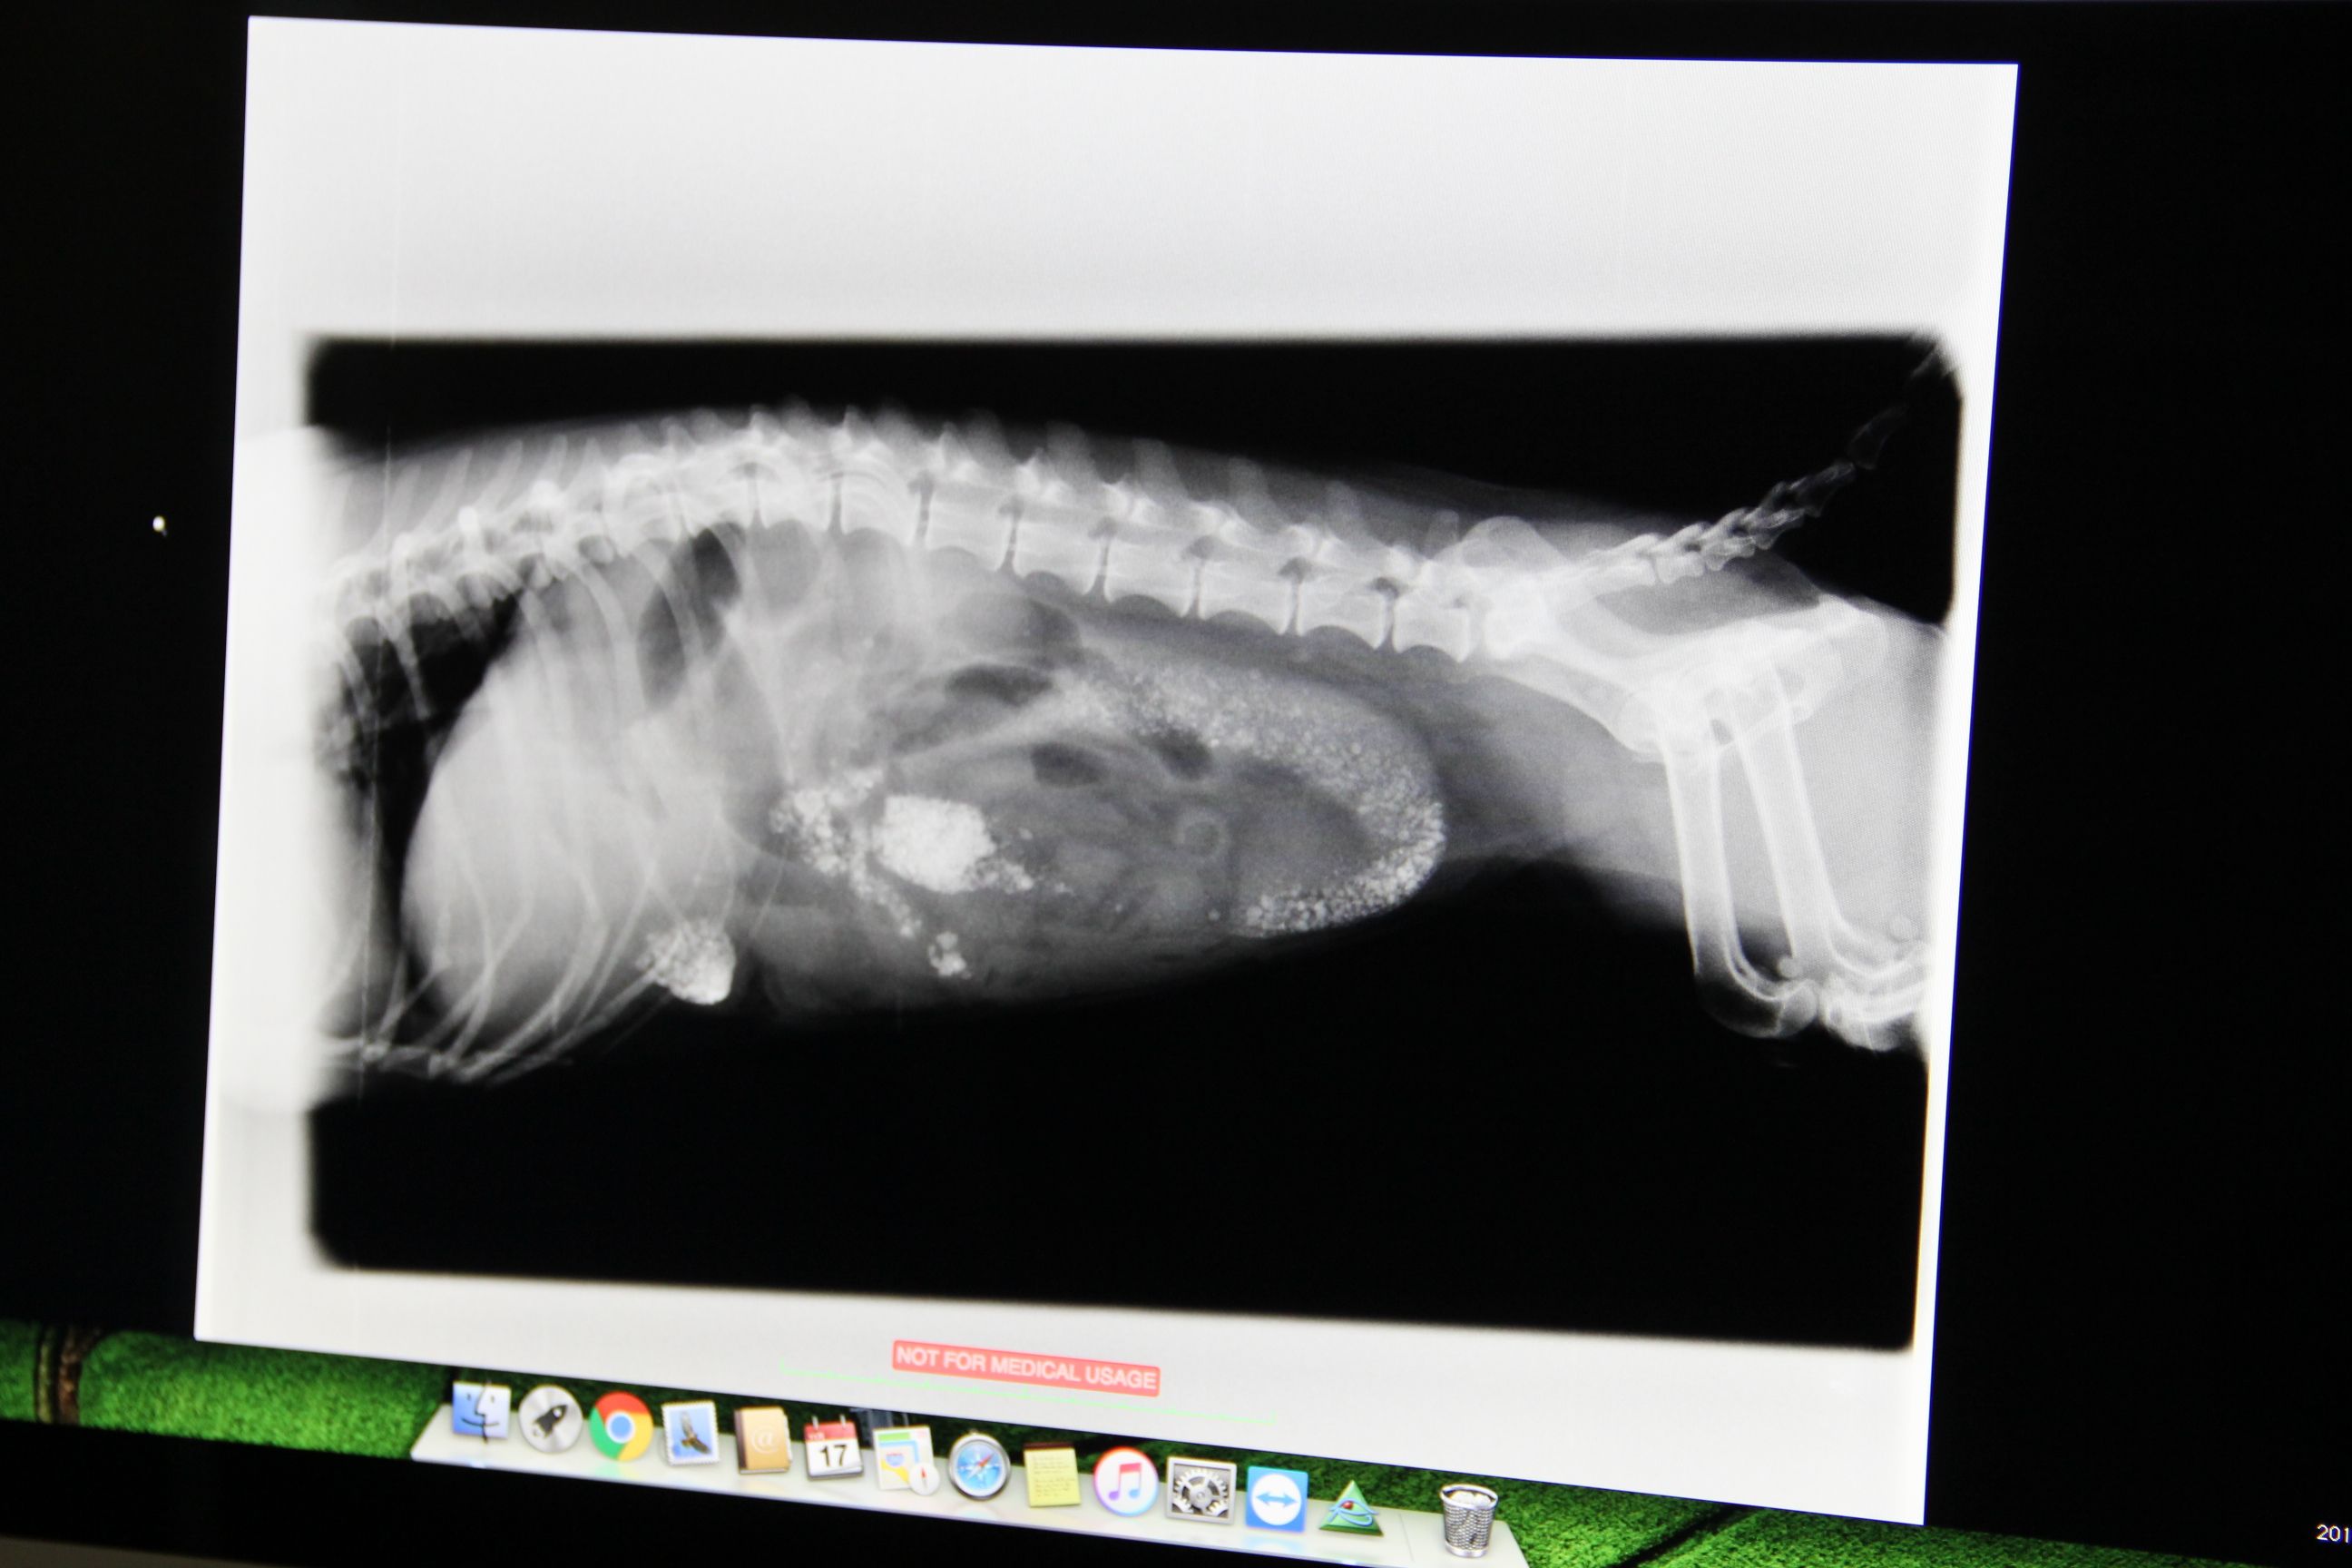

11/17朝の体重:お休み********************************************************プチ、12歳10ヶ月の開腹手術(異物摘出)【術前検査】の続きです。【取り出した異物の写真があります】苦手な方はご遠慮ください。自宅に戻って『プチ頑張れ!』って祈りながら病院からの電話を待ちました。そして23時に着信が先生は何を話すのか?緊張しながら聞いた言葉は・・・『手術無事終了して、プチちゃん今麻酔から覚めたところです』『お会いになりますか?』えーっ、夜遅いのに会いに行っていいの?緊張しながら病院へ【取り出した異物の写真があります】苦手な方はご遠慮ください。術後に撮ったレントゲンまだ砂利が残っていますが流れ出る量なので大丈夫です(退院時にはきれいに無くなりました)腸に穴をあけ、指で砂利を押し出しました腸壁は大丈夫でしたか?大丈夫です最後に液体を流して、穴が開いてないかを確認しました臓器から漏れ出ないことを確認してから縫合しました怖いのが感染症です白血球の値に注意しながら診ていきましょう摘出した異物も見せてもらいましたそして、プチと対面。麻酔から覚めたばかりなのに頑張って起き上がろうとするプチ・・・『プチ、頑張ったね』『また明日ね』って声を掛けました。11/11 16:00 診察11/11 19:40 準備整い次第手術(腸切開術)11/11 23:00 手術終了・麻酔覚醒プチ、頑張りましたプチ、ありがとうプチに申し訳ないのと手術が成功して安心したのとで帰りは運転しながら大泣きのHITONでした続きますプチ大地メレミントに応援クリックよろしくお願いします( 別ウィンドウが開ききるまではそのままでお願いしますm(_ _)m )Instagram登録してみました~プチだいメレミンすたぐらむ 画像をクリックすると移動します今までのハンドメイド作品をまとめました 画像をクリックすると今までの作品をご覧いただけます*******************************************************

11/22朝の体重:プチ4.0kg(withエリカラ)大地5.1kgメレ4.7kgミント:お休み********************************************************プチ、12歳10ヶ月の開腹手術(異物摘出)【術前検査】 【手術終了】 【手術翌日】【手術2日後&3日後】 【手術4日後&5日後】 【退院の準備】の続きです。11/11 16:00 診察11/11 19:40 準備整い次第手術(腸切開術)11/11 23:00 手術終了・麻酔覚醒手術6日後の11/17、プチ退院の日富士山もお祝いしてくれてるのかな9時少し前に病院へ・・・奥からキャーキャー退院直前のレントゲン砂利も出て、きれいになりました木曜日に抜糸来れますか?翌日から連休なので、金曜日にお願いすることに。金曜まで抗生剤出しておきますね朝は飲んだので今日の夜から始めてください安静にしてくださいしばらく食事は4回に分けてくださいプチ、よかったねプチ:『帰ってきたよ~』みんな大興奮安静にしてくださーい大ちゃんはプチの見守り隊横になって休むプチに寄り添ってメレも(ミントはエリカラを怖がって全然近寄ってきません)12歳10ヶ月での開腹手術、痛くて怖い経験をさせてごめんね。プチ本当に頑張ったね。元気になってくれて嬉しいよ。ありがとう大好きだよ続きます&皆さま素敵な週末をプチ大地メレミントに応援クリックよろしくお願いします( 別ウィンドウが開ききるまではそのままでお願いしますm(_ _)m )Instagram登録してみました~プチだいメレミンすたぐらむ 画像をクリックすると移動します今までのハンドメイド作品をまとめました 画像をクリックすると今までの作品をご覧いただけます*******************************************************